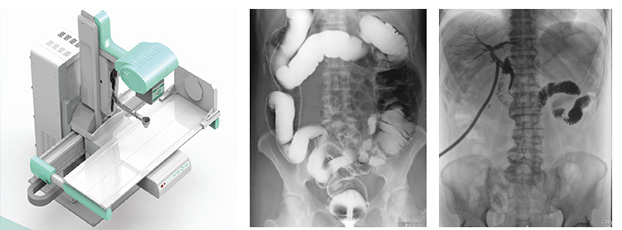

x線數(shù)字胃腸機(jī)讓胃腸疾病診斷更準(zhǔn)確、高效

胃腸疾病是常見的消化道疾病,特別是胃癌、胃息肉、胃潰瘍、胃結(jié)石、結(jié)腸癌、結(jié)腸息肉等病變的早發(fā)現(xiàn)、早診斷、早治療尤為重要。長期以來,胃腸鏡一直是檢查胃腸道病變極為常用的方法,但不少人因?yàn)楹ε伦鑫改c鏡,未能及時(shí)檢查,而延誤了病情。x線數(shù)字胃腸機(jī)是一種不插管、無痛苦的胃腸疾病檢查。

x線數(shù)字胃腸機(jī)

x線數(shù)字胃腸機(jī)主要用來進(jìn)行咽喉部、食道、胃、十二指腸、空回腸及結(jié)腸各種疾病的造影診斷。這款醫(yī)用設(shè)備由高壓發(fā)生器、球管、影像增強(qiáng)器、電動(dòng)檢查床曝光控制臺(tái)和數(shù)字處理工作站組成。

x線數(shù)字胃腸機(jī)的實(shí)質(zhì)其實(shí)是多功能數(shù)字成像系統(tǒng),采用影響增強(qiáng)器把X光轉(zhuǎn)化為可見光,由電荷耦合器將可見光轉(zhuǎn)化為視頻信號(hào),轉(zhuǎn)監(jiān)視器顯示,是一種新的成像方式。流程簡單,操作方便,既達(dá)到診斷目的又減輕病人痛楚。主要特點(diǎn)是準(zhǔn)確、高效、全能。

準(zhǔn)確

采用的平板探測器成像性能優(yōu)異,像素148微米,灰階16bits,圖像清晰準(zhǔn)確,為臨床診斷提供了準(zhǔn)確的依據(jù)。

超大視野的x線數(shù)字胃腸機(jī)

高效

17”×17”(43cm×43cm)碘化銫非晶硅動(dòng)態(tài)平板探測器。超大視野全腹覆蓋。記錄一個(gè)成年人的吞咽過程無須移動(dòng)平板,不產(chǎn)生偽影。對于一些身材高大的患者,無論是頭端,還是下肢,均可全部覆蓋,拍攝無遺漏。

全能

一機(jī)多能,既可以完成消化道造影、靜脈腎盂造影等各種造影檢查,又可以完成DR圖像的拍攝。保證無論靜態(tài)或動(dòng)態(tài)圖像都完美無缺 。

此外,急診患者大多數(shù)都行動(dòng)不便,x線數(shù)字胃腸機(jī)的檢查床不僅可以上下左右四個(gè)方向移動(dòng),還可以正負(fù)方向傾斜,保證了在盡量少移動(dòng)患者和改變患者體位的條件下完成檢查。如果您還想了解“胃腸檢查的方法有哪些?數(shù)字胃腸造影機(jī)效果怎么樣”可以直接點(diǎn)擊該標(biāo)題哦!